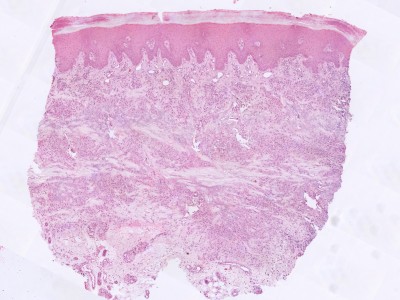

PA:De epidermis is normaal. In de dermis focale degeneratie van collageen met een reactieve ontsteking en fibrose. Soms meerkernige reuscellen. In de dermis een superficieel en diep perivasculair en interstitieel gelegen ontstekingsinfiltraat. Dit infiltraat is samengesteld uit histiocyten, lymfocyten en plasmacellen. Opvallend is de aanwezigheid van necrobiosis omgeven door een wal van histiocyten en lymfocyten. De necrobiotische zone kleurt aan met Alcian blue.